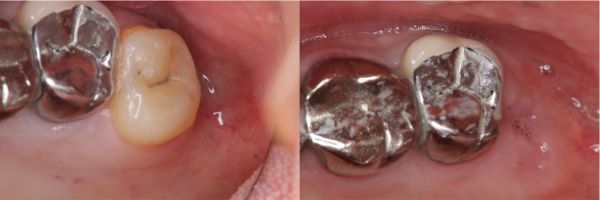

術前、術後比較